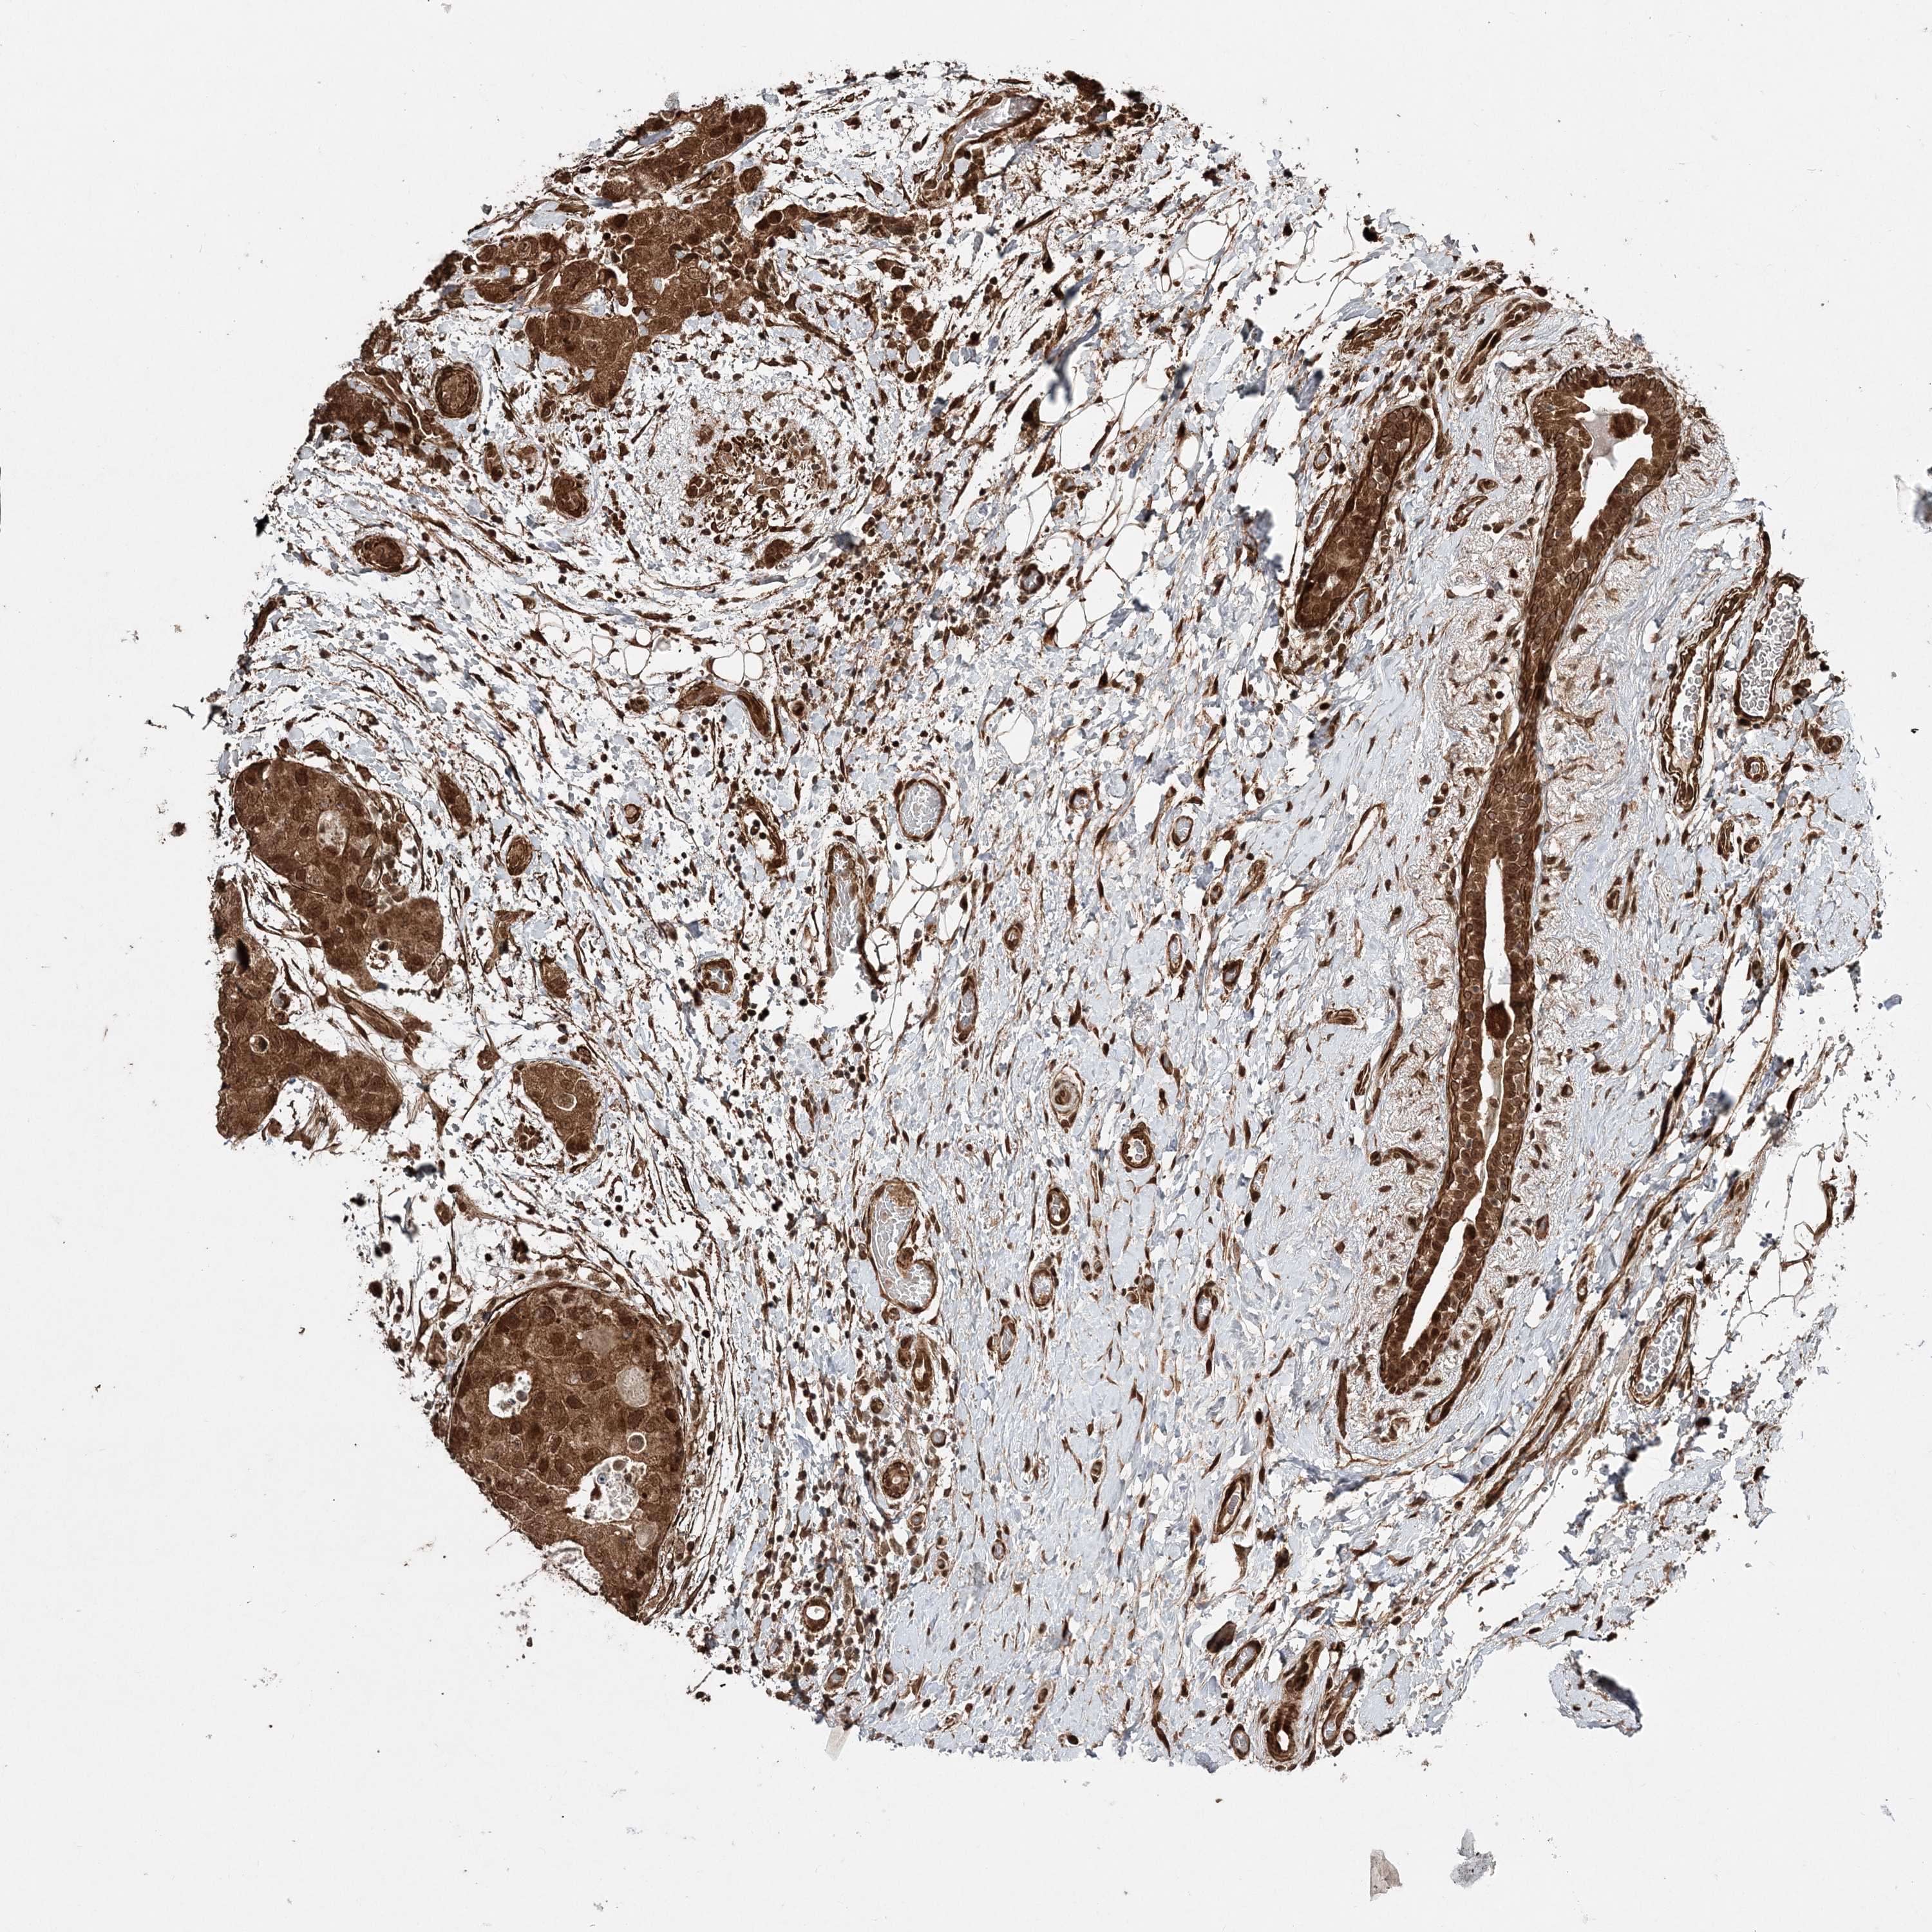

CANCER BREAST CANCER Show tissue menu

BRCA TCGA BRCA VALIDATION PROTEIN EXPRESSION